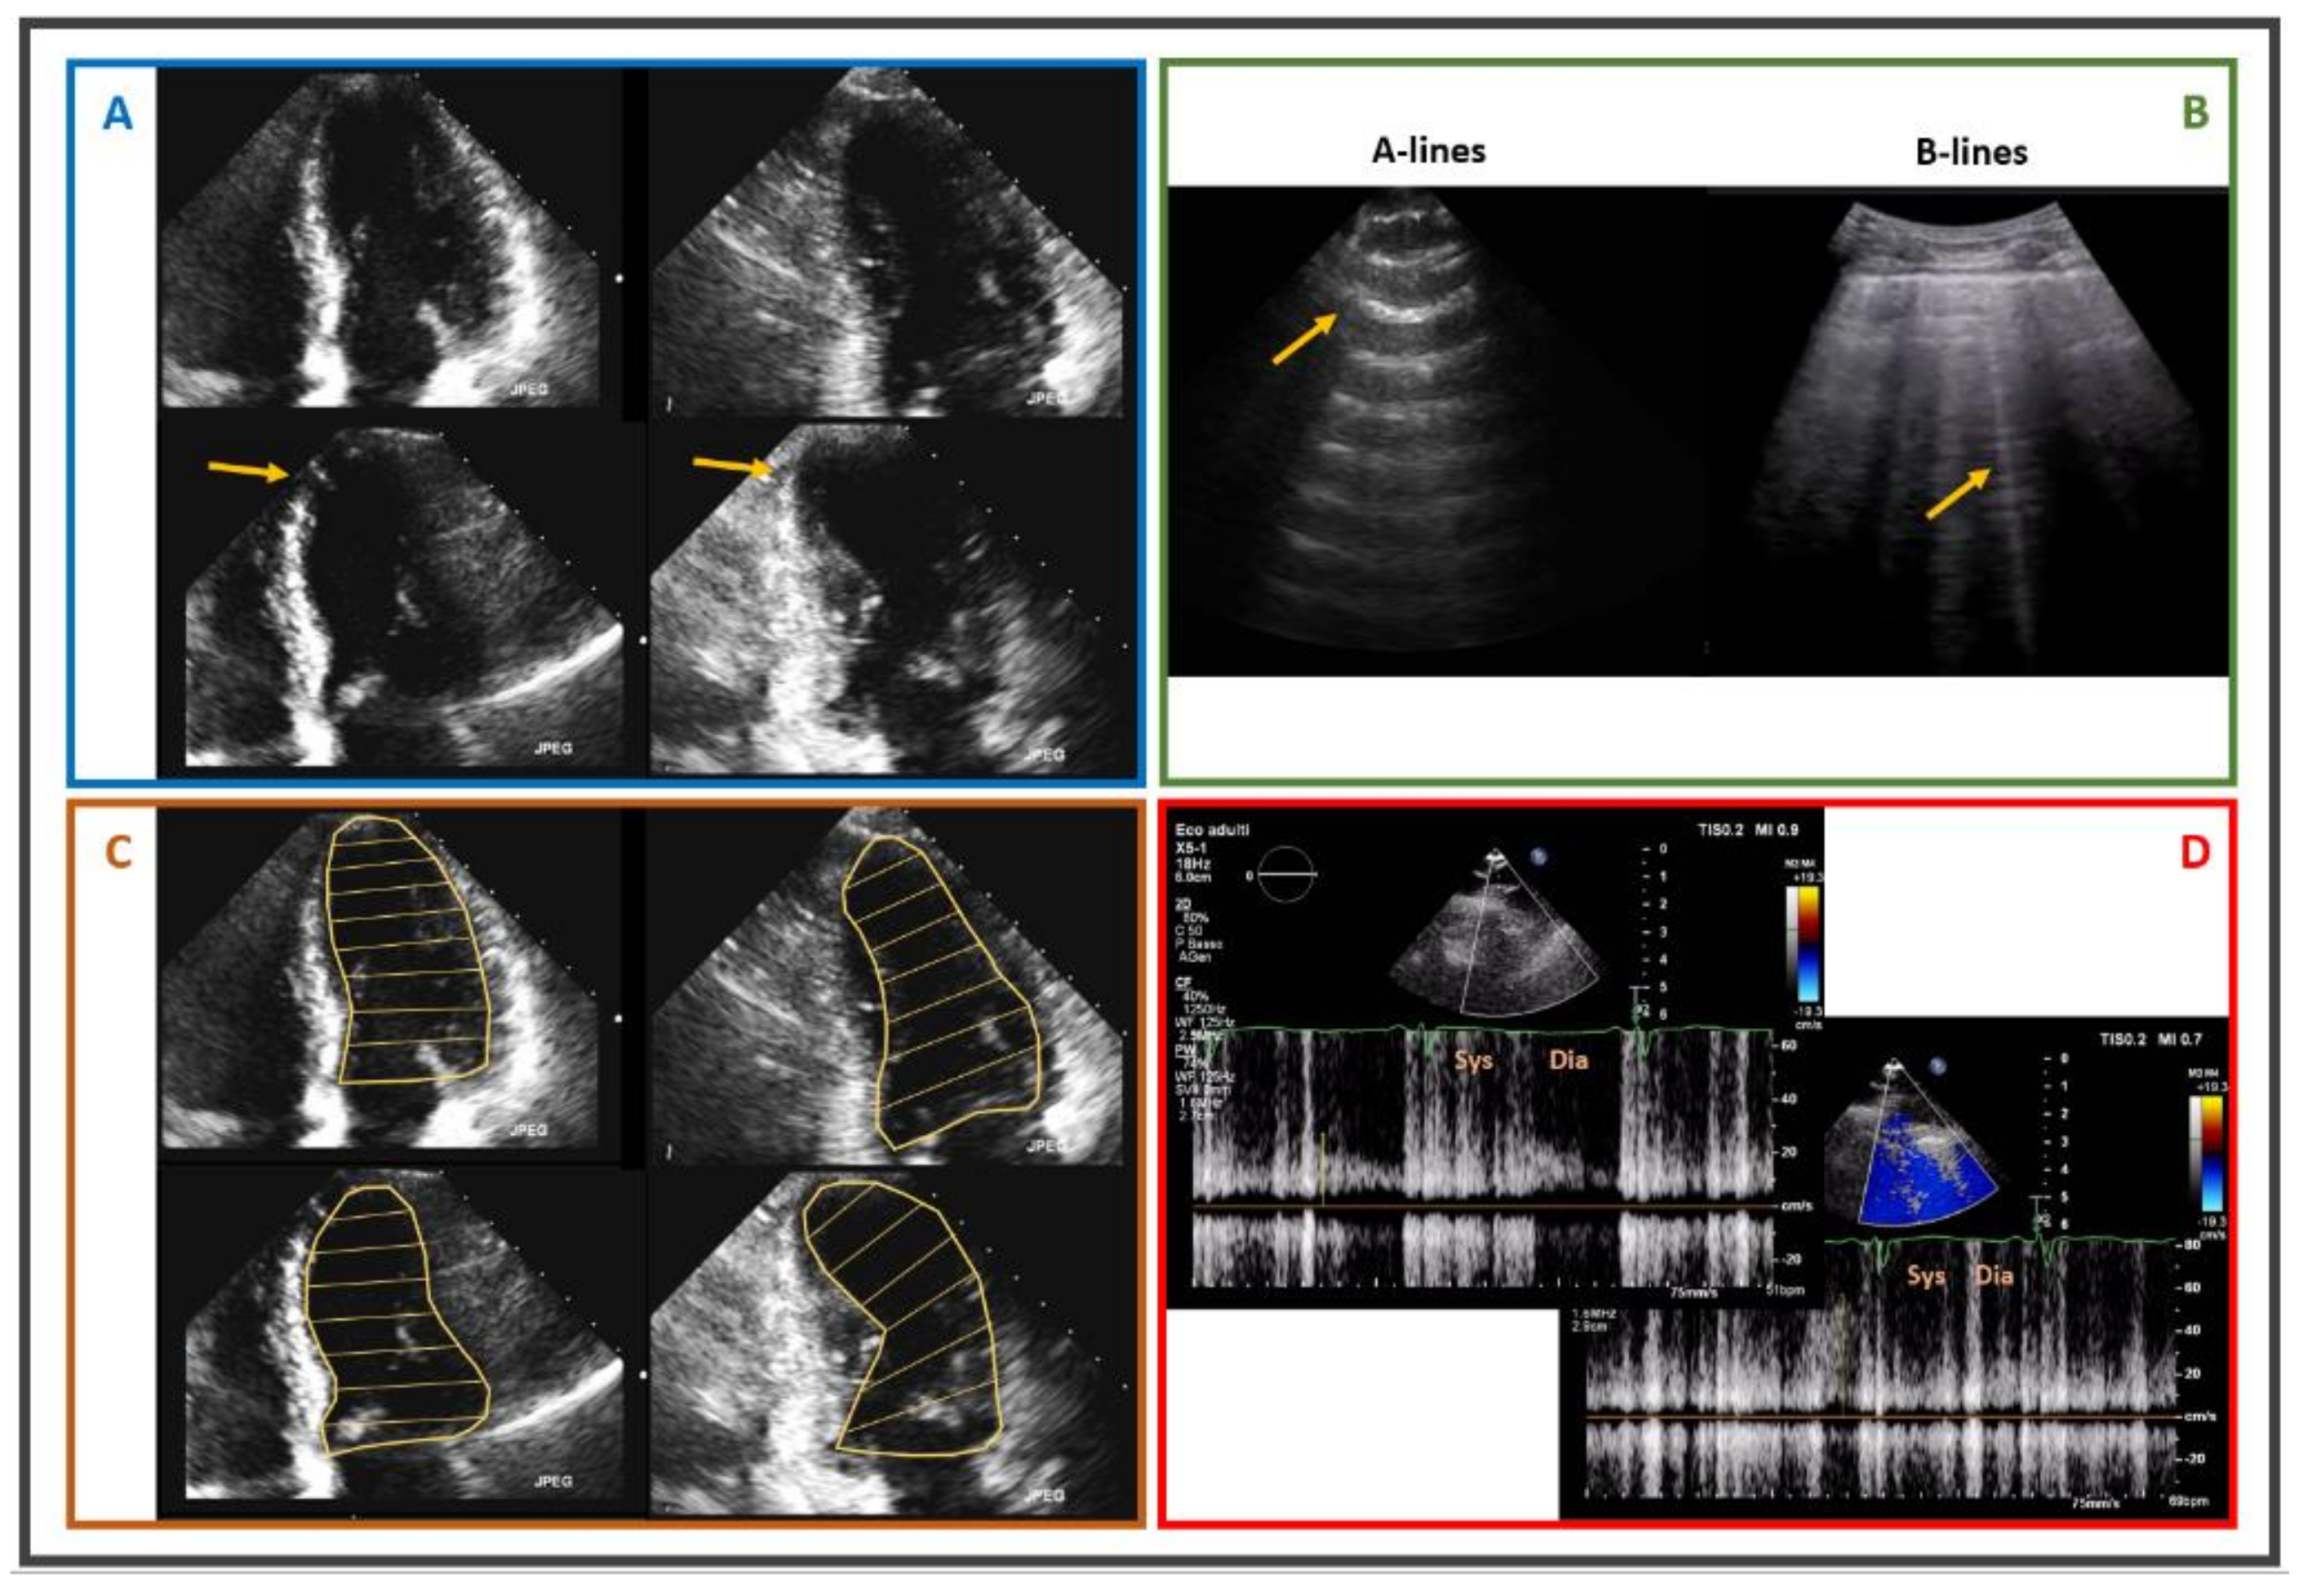

- Picano, E.; Ciampi, Q.; Wierzbowska-Drabik, K.; Urluescu, M.L.; Morrone, D.; Carpeggiani, C. The new clinical standard of integrated quadruple stress echocardiography with ABCD protocol. Cardiovasc. Ultrasound 2018, 16, 22. [Google Scholar] [CrossRef]

- Picano, E.; Scali, M.C. The lung water cascade in heart failure. Echocardiography 2017, 34, 1503–1507. [Google Scholar] [CrossRef] [PubMed]

- Cortigiani, L.; Bombardini, T.; Corbisiero, A.; Mazzoni, A.; Bovenzi, F.; Picano, E. The additive prognostic value of end-systolic pressure-volume relation in patients with diabetes mellitus having negative dobutamine stress echocardiography by wall motion criteria. Heart 2009, 95, 1429–1435. [Google Scholar] [CrossRef] [PubMed]

- Bombardini, T.; Gherardi, S.; Marraccini, P.; Schlueter, M.C.; Sicari, R.; Picano, E. The incremental diagnostic value of coronary flow reserve and left ventricular elastance during high-dose dipyridamole stress echocardiography in patients with normal wall motion at rest. Int. J. Cardiol. 2013, 168, 1683–1684. [Google Scholar] [CrossRef]

- Cortigiani, L.; Rigo, F.; Gherardi, S.; Bovenzi, F.; Molinaro, S.; Picano, E.; Sicari, R. Coronary flow reserve during dipyridamole stress echocardiography predicts mortality. JACC Cardiovasc. Imaging 2012, 5, 1079–1085. [Google Scholar] [CrossRef] [Green Version]

- Picano, E.; Zagatina, A.; Wierzbowska-Drabik, K.; Borguezan Daros, C.; D’Andrea, A.; Ciampi, Q. Sustainability and Versatility of the ABCDE Protocol for Stress Echocardiography. J. Clin. Med. 2020, 9, 3184. [Google Scholar] [CrossRef]

- Ciampi, Q.; Zagatina, A.; Cortigiani, L.; Wierzbowska-Drabik, K.; Kasprzak, J.D.; Haberka, M.; Djordjevic-Dikic, A.; Beleslin, B.; Boshchenko, A.; Ryabova, T.; et al. Prognostic value of stress echocardiography assessed by the ABCDE protocol. Eur. Heart J. 2021, 42, 3869–3878. [Google Scholar] [CrossRef]